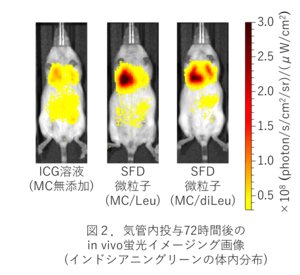

作成したSFD微粒子を電子顕微鏡で観察したところ、成分による大きな違いはみられず、すべてのSFD微粒子が10-20 µmの直径で中空多孔性に富む球状構造を有していました (図1)。